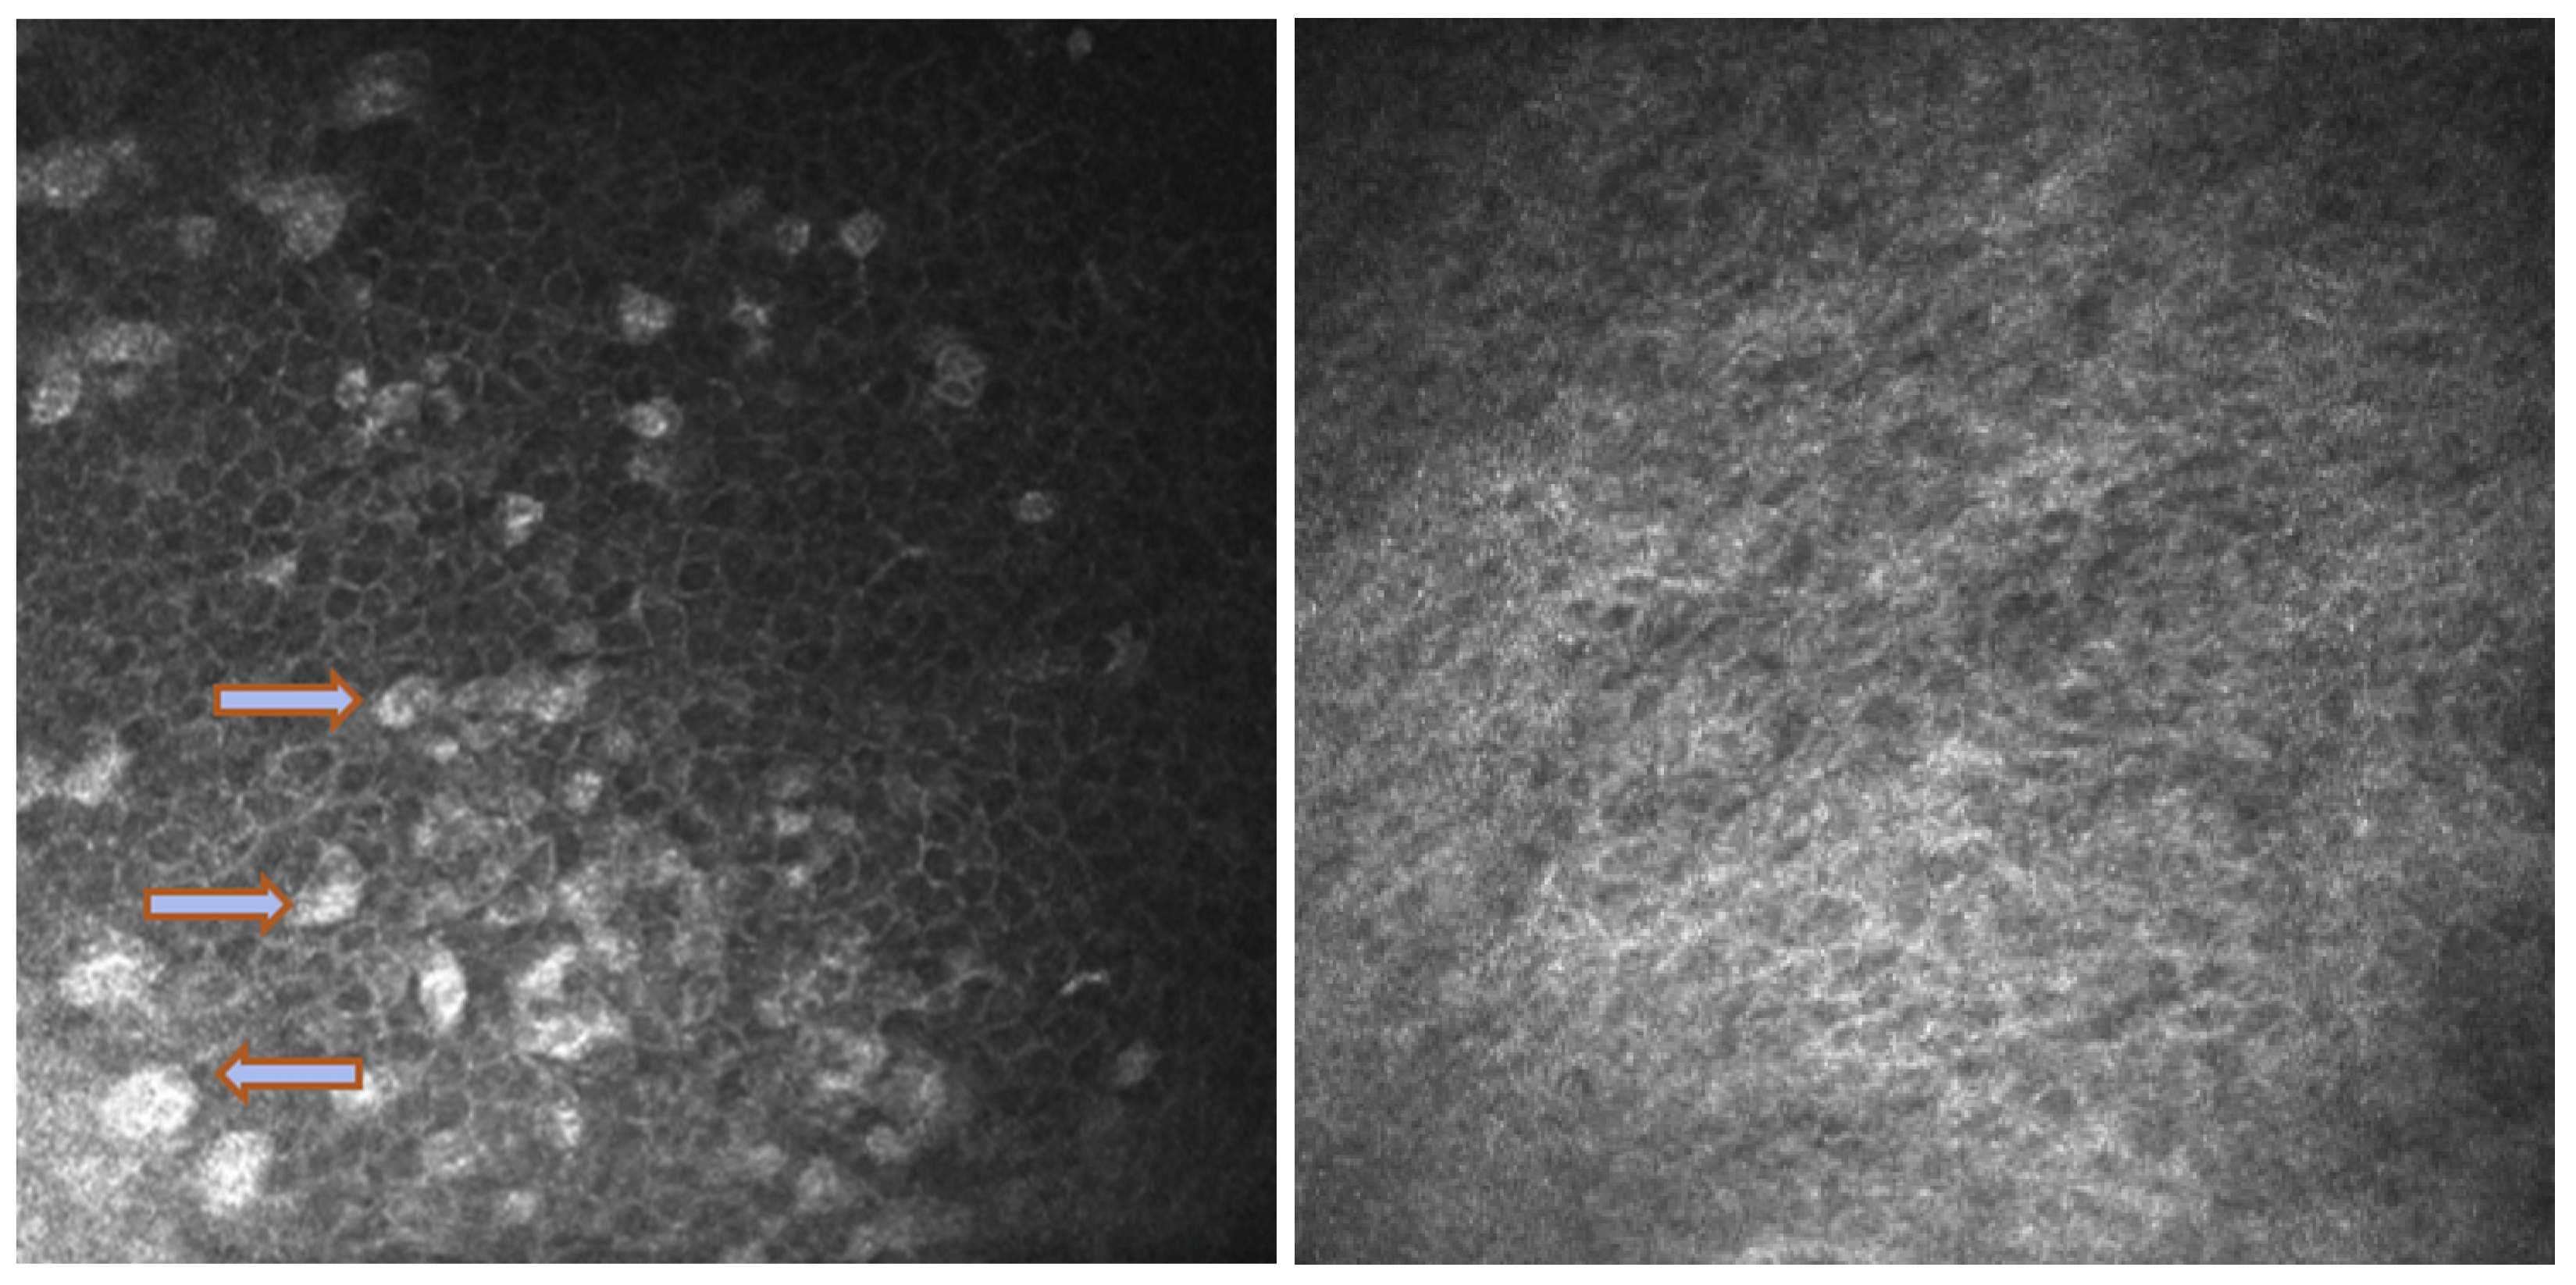

In Group 2, we observed that both eyelids showed mild-to-moderate distorted anatomy at Meibography. At the confocal examination, we observed a decrease in the goblet cell population in the conjunctival epithelium in this group (5.2 cells/mm); in some cases, goblet cells totally disappeared (Figure 5). In tarsal conjunctiva, inflammatory cells were present, and more concentrated around the adenoid lumina of the meibomian glands. We observed several cell infiltrates, composed of a mix of round cells and cells with multilobate nuclei compatible with neutrophils, which were probably a sign of an inflammatory process involving the conjunctiva (Figure 6).

In vivo confocal microscopy provides non-invasive high-resolution images of ocular surface tissues, bypassing the need for biopsy and/or impression cytology. Our in vivo images of bulbar and tarsal conjunctiva, acquired by confocal microscopy, confirmed the reduction in intraepithelial goblet cells as reported in the literature in patients treated with Dupilumab (Figure 5) [7]. Goblet cells are round cells, that occur mainly individually or in clusters, and normally account for 10% of the conjunctival epithelial cells [17]. We found a mean value of 5.2 cells/mm. In addition, the in vivo images show inflammatory cells in the tarsal conjunctiva and around the adenoid lumina. We assumed that the inflammation could be the cause behind the dropout of glands.

Figure 5. In vivo images of bulbar conjunctiva of a naive patient (left) and treated patient (right). Note the presence of intraepithelial goblet cells (arrow) on the left, while they are absent in the image on the right.